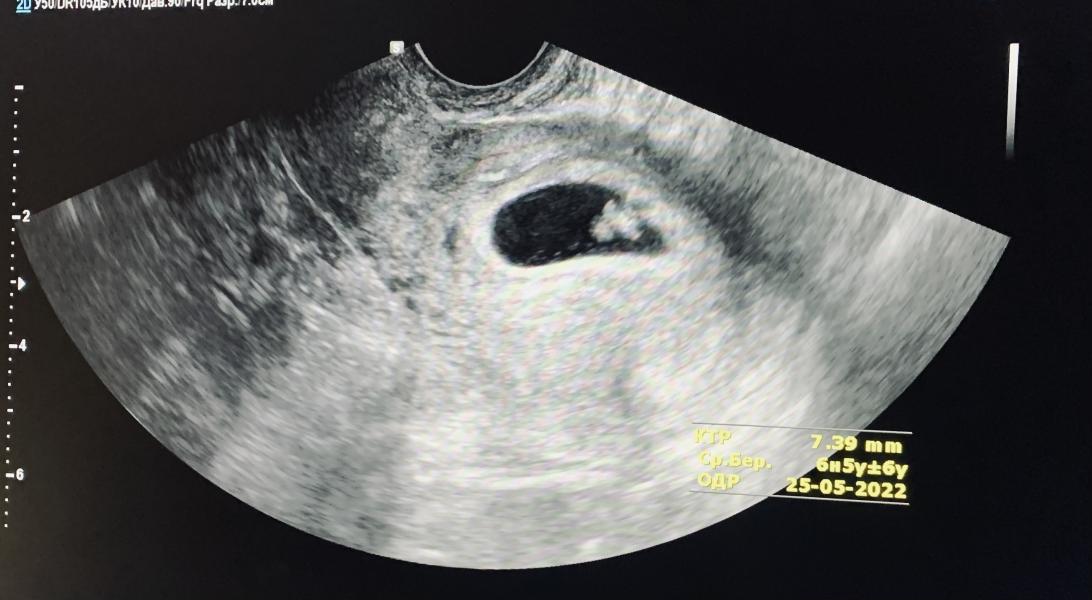

Бы на узи, назначали повторное 24 сентября. Так как увидели только ПО, теперь видно все, эмбриончик на месте, растёт наше сокровище, сердечко стучит 🙏😭🥰

P.S первое фото крохи😍

экран разрешили сфоткать, у них сломался принтер 🥺